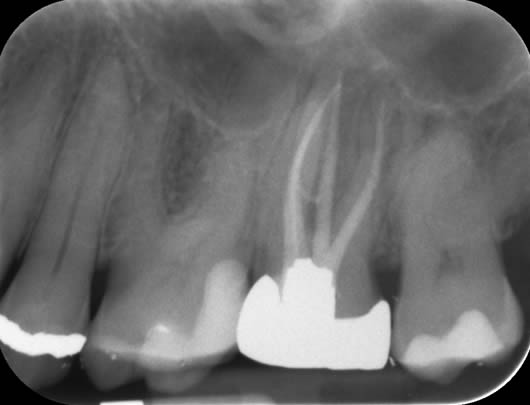

Case 2: Root canal treatment – the elusive MB2 canal.

In approximately 90% of upper first molars there are four root canals. The fourth canal (MB2) is difficult to locate and can be very challenging to negotiate to its end. It is a very common occurrence that this canal is missed during treatment and this can lead to failure. We use a dental microscope, which magnifies the tooth and assists us in locating this canal. We then use a series of tiny instruments in a specific technique, honed over many hours of practice, to negotiate to the end of the canal. This case shows the filling of all four canals.

Pre-operative radiograph UR6

Post-operative radiograph UR6